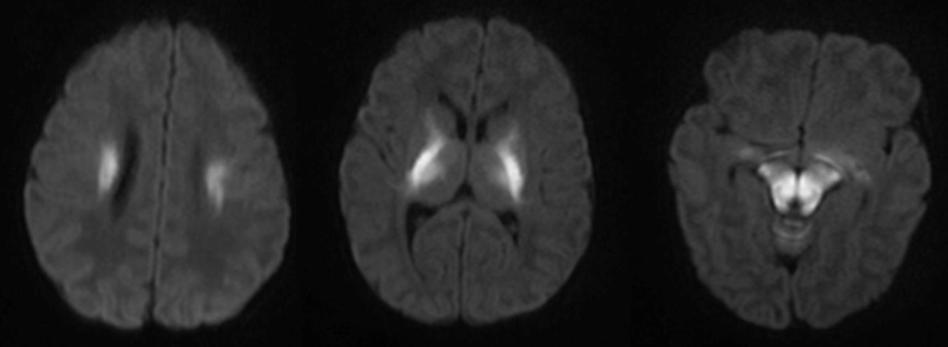

男性,出生2月余,喂食差,癫痫,呕吐,低血糖。

答案:枫糖尿病。枫糖尿病是由α-酮酸脱氢酶多酶复合体功能缺陷引起的常染色体隐性遗传病。婴儿起病的白质脑病要想到枫糖尿病。影像上要注意和Leigh综合征鉴别。Leigh综合征多在10岁以前发病,以婴幼儿多见;神经系统的主要表现为抽搐、卒中发作、眼外肌麻痹、痴呆、共济失调、视神经病变等。Leigh多为双侧对称性分布,病变形态不规则,大小不等,呈斑块状;病变主要累及双侧壳核及导水管周围灰质,也可累及丘脑(尤其是背内侧核)、小脑齿状核、脑干、脑白质和皮质均可受累;MRI呈长T1、长T2信号,T2-FLAIR和DWI像病变信号多不均匀。枫糖尿病特点为弥漫性的脑白质水肿,遍及大脑和小脑半球的TW2I上的高信号,尤其在基底节及脑干区。典型表现为侧脑室旁、基底节区、脑干、小脑T2WI及DWI上的高信号影,DWI显示的更加敏感;MRS在0.9ppm处可发现一个相对特异性的宽峰;同时可见NAA峰的下降及Lac峰的升高。